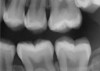

CBCT can also be used in this same manner to perform an even more common task, bitewing images, which are clinically indicated as often as every 18 to 24 months. For hygiene patients whose films require updating, CBCT offers a “patient-friendly” approach. Given that these films, which are usually performed intraorally, are often taken on an hourly basis in the typical general practice, the technology can be well utilized while also increasing comfort and satisfaction among patients. In addition, due to the expanded field of view that can be achieved with these extraoral CBCT images, they can often be more diagnostically valuable than images produced with an intraoral sensor (Figure 1 and Figure 2).